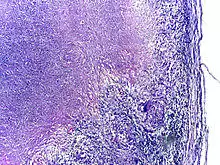

Microscopy of tuberculous epididymitis. H&E stain

Tuberculosis is classified as one of the granulomatous inflammatory diseases. Macrophages, epithelioid cells, T lymphocytes, B lymphocytes, and fibroblasts aggregate to form granulomas, with lymphocytes surrounding the infected macrophages. When other macrophages attack the infected macrophage, they fuse together to form a giant multinucleated cell in the alveolar lumen. The granuloma may prevent dissemination of the mycobacteria and provide a local environment for interaction of cells of the immune system.[63] However, more recent evidence suggests that the bacteria use the granulomas to avoid destruction by the host's immune system. Macrophages and dendritic cells in the granulomas are unable to present antigen to lymphocytes; thus the immune response is suppressed.[64] Bacteria inside the granuloma can become dormant, resulting in latent infection. Another feature of the granulomas is the development of abnormal cell death (necrosis) in the center of tubercles. To the naked eye, this has the texture of soft, white cheese and is termed caseous necrosis.[63]